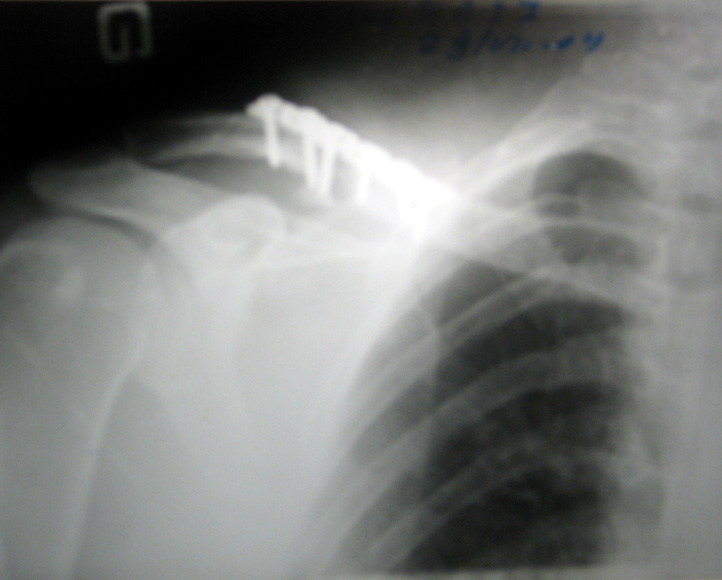

Случилось это в Сентябре прошлого года, на дёрте Олешки, в Измайловском парке. Я тогда 100% донором был, а адреналину хотелось... Ну вобщем перелетел я прилично на верблюде.

Результат - сломанная ключица, три ребра, лопатка. Самые сильные воспоминания, это как я верхушки деревьев увидел, очнулся - пот градом, дышать не могу, но ничего не болит. Хорошо друзья сомной были, довезли до больницы. Скоро лягу железочку эту выкручивать.

Нажмите на изображение для увеличения

Название: ________842.jpg

Просмотров: 572

Размер:	100.6 Кб

ID:	5296

Я так понимаю на фото сломанная ключица, у тебя привезали плостину металлическую а у моего друга на снимке прямо в ключитцу вбид штыри (металлический), сочуствую неприятная штука...